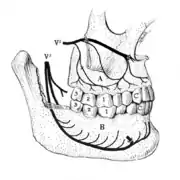

V2: maxillary division of trigeminal nerve, V3: mandibular division of trigeminal nerve, A: the superior alveolar nerves and plexus, B: the inferior alveolar nerve and plexus running in the body of the mandible.